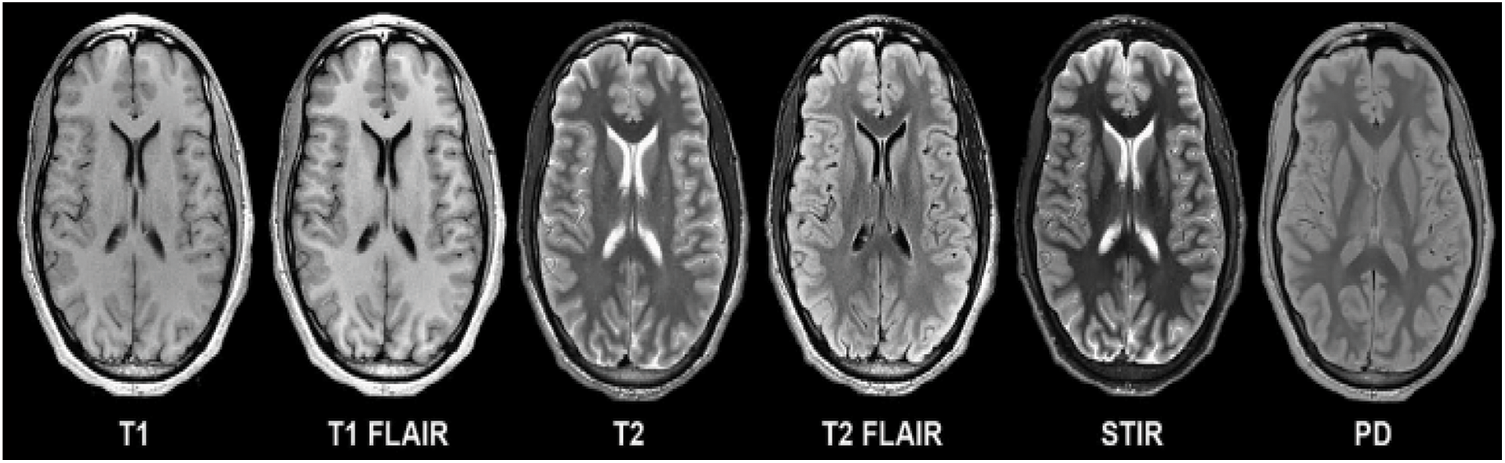

Tumors can have a big effect on how long people live. The high-grade subtype is a dangerous type that kills about 14,000 people a year. These irregular growths of cells in the brain cause pressure in the parts of the brain that are near them. These abnormalities make it hard for the brain to control the normal activities of the body. People who have these abnormalities have light-headedness, pain in the head, fall over, become paralysed, and so on to name a few. Grades 3 and 4 are more likely to damage the healthy tissues that surround the brain, and they often have to be fixed with surgery. To get rid of these bad groups of cells, doctors use things like drug therapy, particle emission therapy, and so on. In spite of a lot of work and progress in technology over the last few decades, people who have tumors still don’t live more than a few years. Computer Tomography (CT), X-rays, and Positron Emission Tomography (PET) are some of the imaging techniques used to find the abnormalities on the brain. There are also different types of Magnetic Resonance Imaging (MRI) techniques that can show these abnormalities. Few of the modes are shown in the Fig. 2 below.

Figure 2: Various image modalities of brain

In Fig. 2, T1 and T2 are shown as weighted imaging, while T1 FLAIR and T2 FLAIR are shown as weighted Fluid Attenuated Inversion Recovery, which is what they are called. A multi-grade detection of the brain is a step toward understanding these problems, but there are still problems with segmentation accuracy and classification accuracy. There is a lot of noise, a lot of intensity variation, a lot of variation in tumor size, and a lot of other things that radiologist and computer vision researchers have to deal with. In clinical terms, imaging is the main tool used to look for abnormal cell growth in the brain. These imaging techniques give information about things like where the abnormal growth is and how dense it is, which helps surgeons a lot and also helps them see how well treatment is working. In addition to the above, they show quantitative image features like the variance and similarity between the intensity of nearby pixels [3]. Many scientists think that when they use this information with a machine learning algorithm, they will make great progress in the diagnosis and treatment of tumors. Machine learning studies in the past used a variety of steps to separate images into normal and abnormal ones. These steps included analysing the data, finding the most important features, and reducing the number of properties that were found so that the process was more efficient. Experts in the field, such as radiologists and doctors, were the ones who did the majority of the work in this area. It is a very clumsy and tiring thing to do for someone who isn’t very good at it. Extracting features from images is the first step in traditional machine learning. The accuracy of segregation is mostly dependent on the features that are retrieved. Thus, spotting a tumor in the brain’s complex composition is a very important process that is very much influenced by the way the brain is segmented. Radiologists used to do manual segmentation in the early days, but this took up a lot of their time, which made them want to use an automatic or semiautomatic process to find tumor cells.